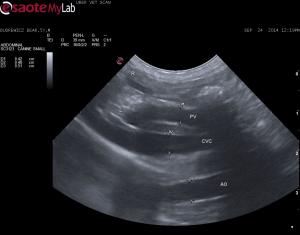

– looks like the PV:Ao ratio is normal at the PH and no anomolous blood vessels seen entering the CVC, at least from what I could see when scanning through the PV and CVC

Great shot of the pv with

Great shot of the pv with the pancreatoduodenal vein coming in on top. With this solid PV volume at the branching you can rule out ehpss but you have to get th ebranches in like you did otherwise you can miss a gastrocaval or gastroazygios shunt that branch off toward th epylorus right before the pv branches into the right and left branches in the liver. The portal vein hypoplasia is likely the dx and yorkies are the poster child for this. Its a medical tx and needs parenhcymal bx to confirm. Wihtout getting specific because Im not a pathologist you will have parenchymal microsopic shunts in PVH and lack of development of portal triads and sinusoids on ehpss but you can have both as well. Whe  both occurs then ehpss correction often becomes problematic with portal hypertension developing.